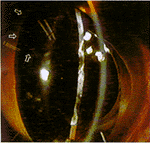

:8只猴子的8只眼使用了晶状体注入法。为防止注入的液态硅酮漏出,开发了一种活体上应用的硅酮塞,在液态硅酮凝聚之前封闭囊膜口。在晶状体上方做小型环型撕囊后,行囊袋内晶状体超声乳化手术,然后用塞子闭合撕囊口。通过塞子上的传输管道,将硅酮混合物注入到囊袋内,手术后1周和3个月,进行自动验光仪验光,测定4%匹罗卡品滴眼前和滴眼后1小时的调节力变化。

:8只眼中5只能注入晶状体,测定了其中4只眼的屈光状态。调节幅度从1.0到4.5D,平均2.3±1.3D(术前值:8.0±2.0D)。术后3个月所有眼中均有浓密的后囊混浊,影响了屈光检查。